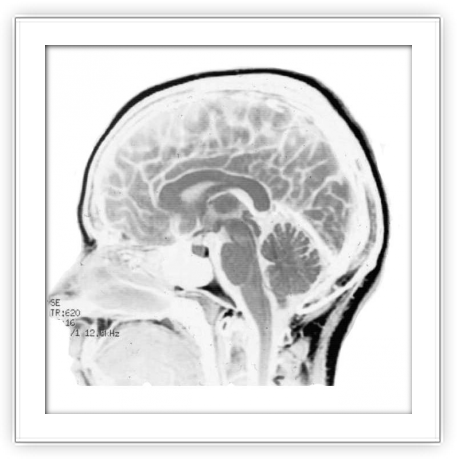

Neurología de la música y del lenguaje